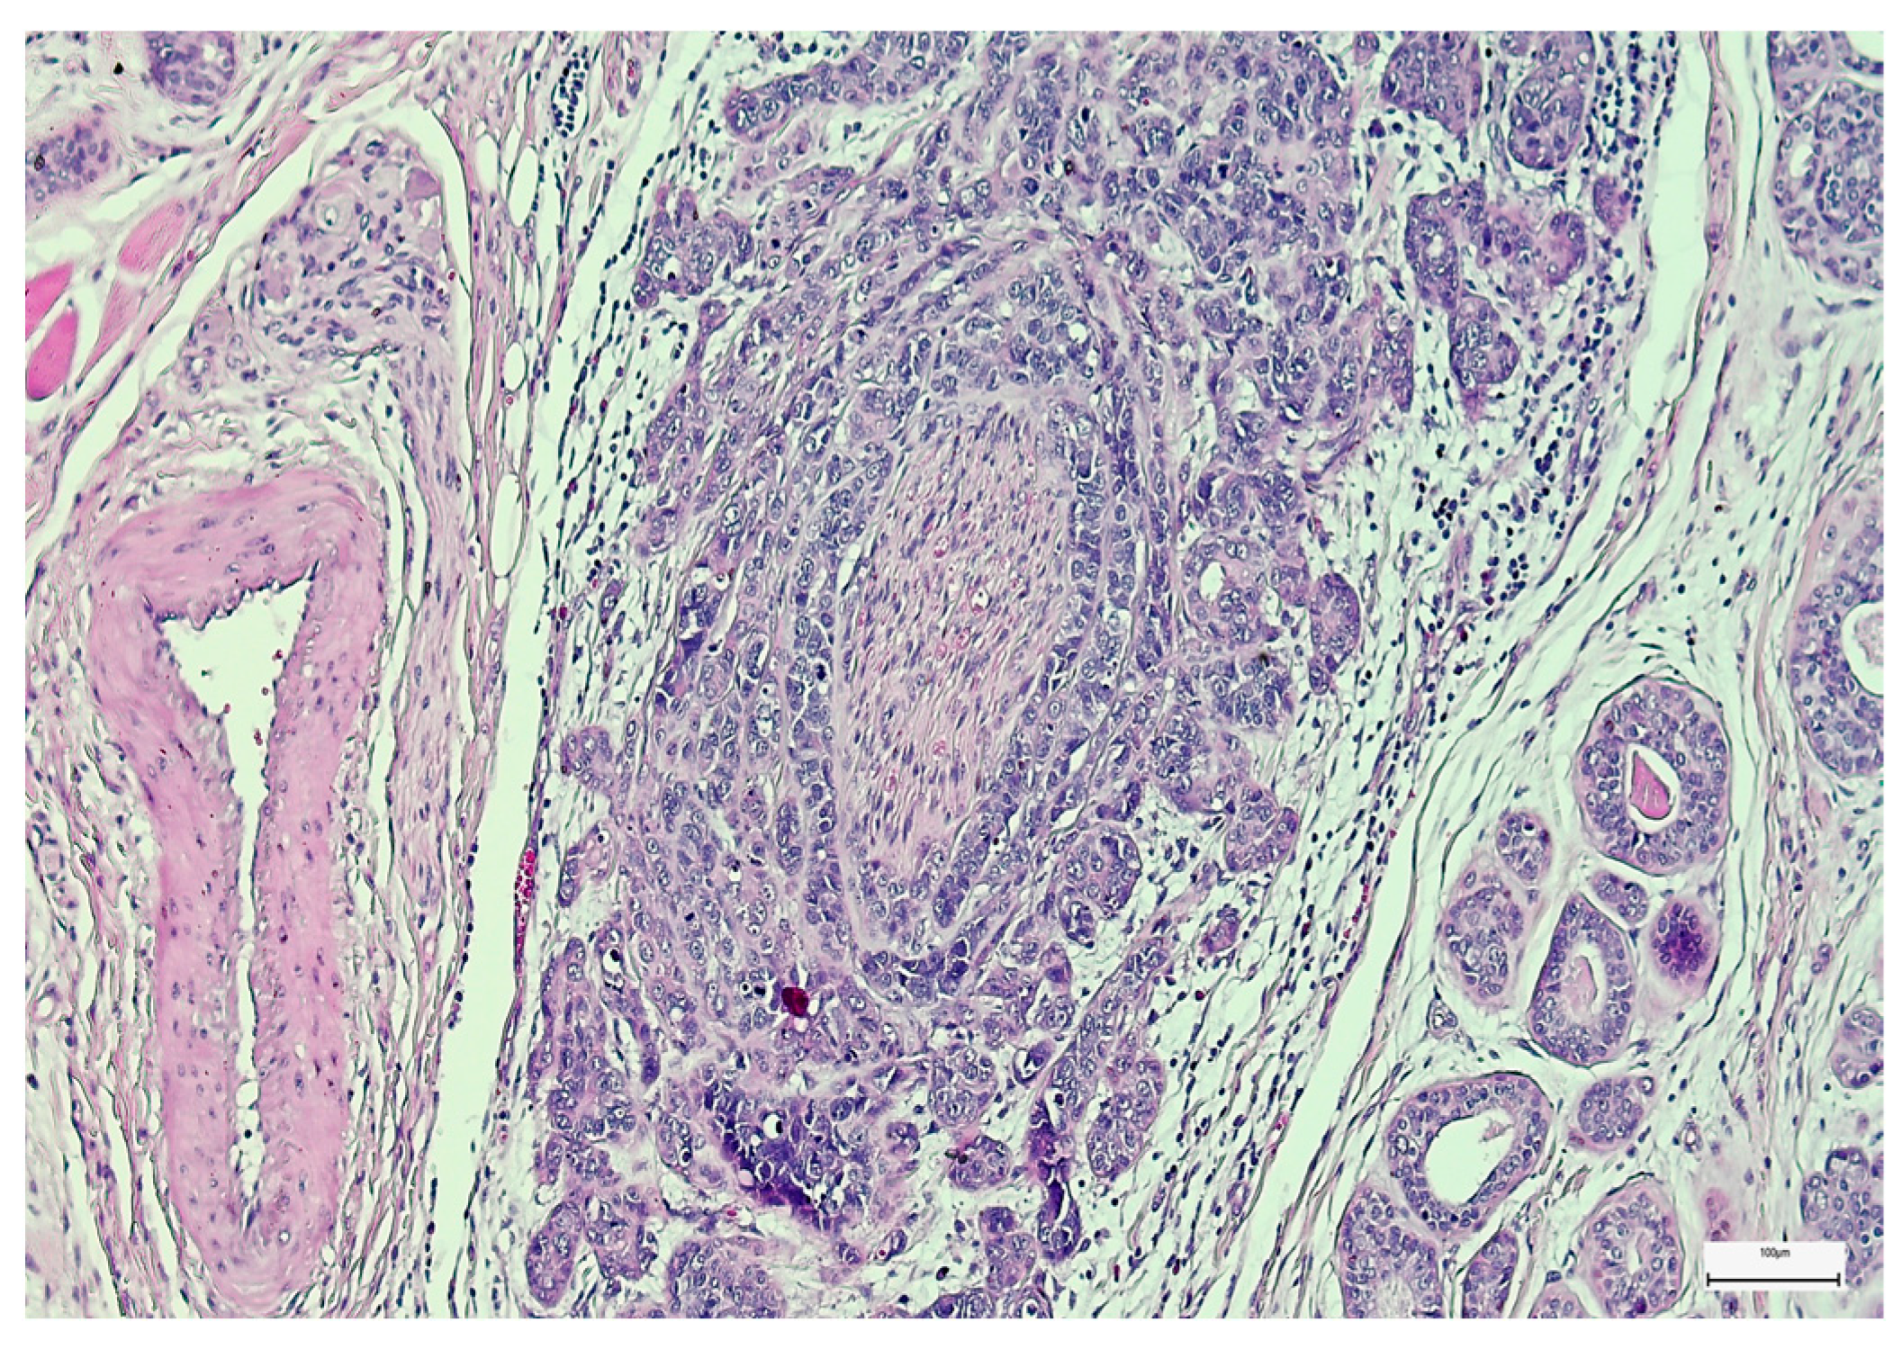

3. Results

3.2. Qualitative and Semi-Quantitative Assessment of SOX-2 and EZH-2 Immunoexpression